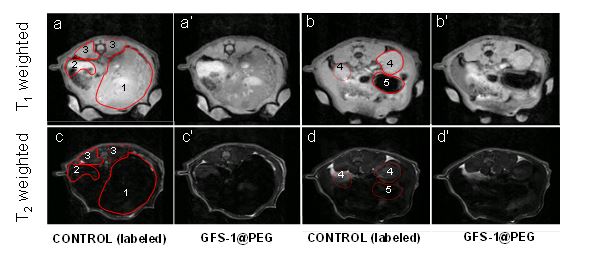

• CIBERBBN

Desarrollan nanopartículas que mejoran el contraste en imágenes de resonancia magnética y facilitan el diagnóstico clínico

11/04/2018